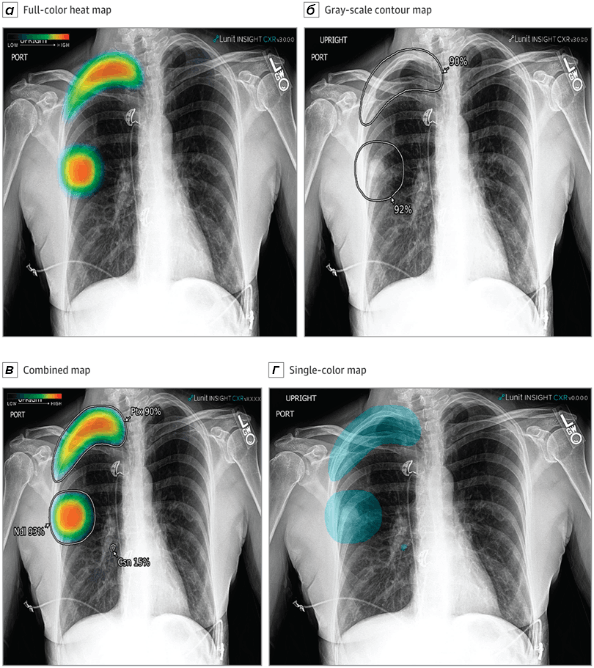

Рисунок 4. ИИ в медицинской визуализации: робот анализирует рентгеновский снимок легких. На панели (а) показана рентгенограмма грудной клетки с наложенной картой внимания (тепловой картой) — визуализацией того, на какие зоны модель обращает внимание при анализе. Цветовая шкала (от синего к красному) показывает степень важности каждого пикселя для принятия решения о диагнозе. Такие карты — это инструмент объяснимого ИИ (explainable AI), который позволяет врачу увидеть, почему алгоритм пришел к тому или иному выводу.

Но есть свет в конце туннеля. Методы визуализации активации — например, карты внимания (attention maps), которые мы видели на рисунке 4 — позволяют частично «развеять туман». Такие карты показывают, на какие области снимка модель обратила внимание при принятии решения. Это не полная прозрачность, но уже возможность врачу увидеть логику алгоритма: «Ага, вот здесь сеть увидела подозрительное уплотнение, и вот здесь — еще одно». Вряд ли пациент согласится лечиться от болезни, диагностированной на основании полного мрака; но если модель хоть как-то может объяснить свои решения, доверие растет. Решение этой проблемы кроется в создании систем xAI. Объяснимый искусственный интеллект (Explainable AI, xAI) — это направление исследований и набор методов, целью которых является создание систем ИИ, способных предоставлять понятные для человека обоснования своих решений и действий. Такие системы уже существуют и тестируются — например, OpenAI o1, DeepSeek-R1 или российская T-pro 2.0.